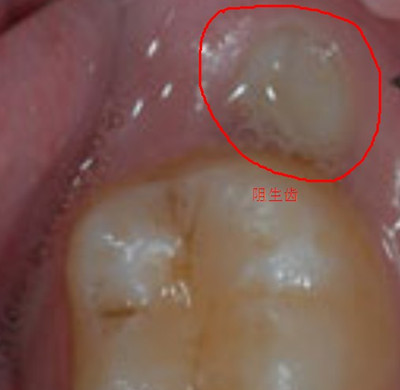

点击【在线咨询】直接问医生!方便!快捷!有时老是会感觉牙齿莫名的疼痛,甚至连脸颊都会引发肿胀,这一切可能是智齿在作怪,智齿的生长是极为不规律的,一些不正常的智齿会严重的影响我们的身体健康,因此像这些发展异常的智齿,必须要进行拔牙。

医生介绍,在进行智齿拔除前,医生都会先对口腔进行全面的检查,如口腔内有龋病炎症,就需要先治疗才能进行牙齿拔除,这会增加拔牙的费用。另外智齿生长位置的特殊性及结构的复杂性,都决定了其所需的花费。

拔智齿难易程度的不同价格也不会一样,有些顾客朋友由于智齿结构较为复杂,在拔智齿前需要进行拍X光片等相关操作,因此根据智齿所处位置及病变程度的不同,导致了拔智齿费用的不同。因此拔智齿难度较普通的拔牙难度偏大,因此拔智齿一定要到正规、专业的牙科机构进行!